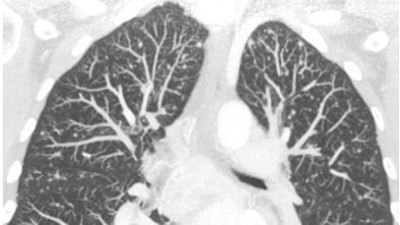

Smaller pixels certainly came in handy in one proffered example: a six-second high-resolution scan of a patient with medullary thyroid cancer. The image showed multiple tiny metastases throughout the lungs, many of which were in the submillimeter range.

| High-resolution CT of the chest performed with 40 x 0.625-mm collimation within six seconds. Images were reconstructed with a 768 x 768 matrix, yielding 0.45-mm pixels that take full advantage of the increased resolution of these machines. Note the multiple small metastases in this patient with medullary thyroid cancer. Image courtesy of Dr. Mathias Prokop. |